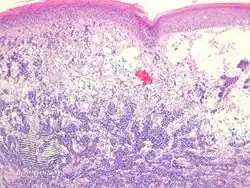

Photomicrographs of a typical Merkel-cell carcinoma at a 4x, b 40x, and c–d 100x objectives. Hematoxylin and eosin staining demonstrates small, undifferentiated cells with high N/C ratio and scanty cytoplasm. Typical immunopanel demonstrates positive staining with e cytokeratin AE1/AE3 (100x oil immersion), f CK 20 (100x oil immersion), and neuroendocrine markers such as g chromogranin (100x oil immersion).[24]

Diagnosis of MCC begins with a clinical examination of the skin and lymph nodes.[25] Following clinical exam, definitive diagnosis of Merkel cell carcinoma (MCC) requires examination of biopsy tissue to identify its histopathologic features.[3][25] An ideal biopsy specimen is either a punch biopsy or a full-thickness incisional biopsy of the skin including full-thickness dermis and subcutaneous fat. On light microscopy, MCC shows basaloid tumor nests with neuroendocrine features ("salt and pepper" chromatin, scarce cytoplasm, and brisk mitotic activity).[3][25] In addition to standard examination under light microscopy, immunohistochemistry (IHC) is also generally required to differentiate MCC from other morphologically similar tumors such as small cell lung cancer, the small cell variant of melanoma, various cutaneous leukemic/lymphoid neoplasms, and Ewing's sarcoma. Neuroendocrine molecular markers such as synaptophysin or chromogranin A are characteristic of MCC and other neuroendocrine tumors, while other markers such as PAX5 or cytokeratin 20 can distinguish MCC from these tumors.ref name=Kervarrec2019/>[4] Longitudinal imaging may also help in ruling out a diagnosis of metastatic small cell lung cancer. Once an MCC diagnosis is made, a sentinel lymph node biopsy as well as other imaging is recommended as a part of the staging work-up needed to determine prognosis and subsequent treatment options.[3][25]